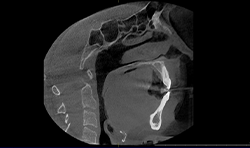

As of March 2019, the patient has been in combination therapy, wearing her aligners and sleep appliance for just more than two months. We’ve had three follow-up appointments to ensure compliance and comfort of the therapy. One adjustment has been made to the ASA, advancing the mandible forward to relieve residual snoring. At the third recall appointment, per the treatment plan, the next set of aligner trays were fitted with the ASA to ensure proper fit and evaluate for discomfort. Radiographs were taken showing stable condyle positions with improvements to the oropharynx (Fig. 8). A sleep study will follow to evaluate efficacy of the therapy now that the patient has been stabilized.

Fig. 8